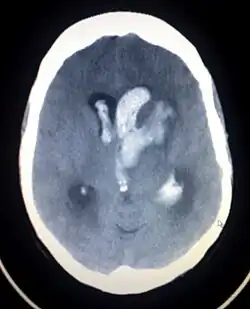

A non-contrast CT scan (computed tomography) of the brain is commonly used as the initial imaging modality in suspected cases of intracranial hemorrhage. CT is preferred in emergency settings due to its speed, availability, and high sensitivity for detecting acute brain injuries, enabling rapid triage and surgical decision-making. Examples of brain diseases that require urgent intervention are: large-volume hemorrhage, brain herniation, and cerebral infarction. Additional advantages of CT imaging include its effectiveness in detecting bony fractures, vascular injuries, and cerebrospinal fluid (CSF) leaks.

A swirl sign on CT imaging— representing areas of low density with surrounding areas of high density— suggest active intracranial bleeding. The presence of this sign is associated with an increase in risk of death within one month and a poor functional prognosis at three months among survivors.[6]

The size of the hemorrhage can vary, ranging from small, asymptomatic lesions to large hematomas causing mass effect and increased intracranial pressure. Follow-up CT imaging is recommended to monitor hematoma expansion, ventricular extension, or progressive cerebral edema, all of which are associated with poorer outcomes.

CT angiography (CTA) may be used to assess active bleeding. The presence of a "spot sign"—contrast pooling within the hematoma on delayed-phase imaging—suggests ongoing hemorrhage and is considered a predictor of hematoma and worse clinical prognosis.[1]